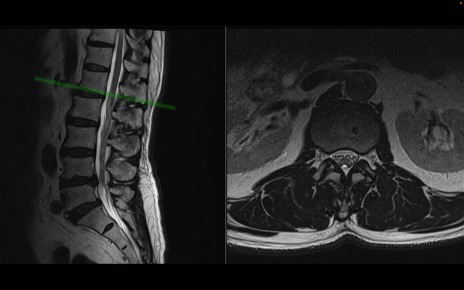

【整形】TIPS症例2 腰椎MRI 横断像と矢状断像

【症例】70歳代男性

【主訴】左下肢痛

【現病歴】2週間前くらいから腰痛、左下肢痛あり。左臀部から大腿、下腿外側のしびれが常時ある。歩行とともに同部位の痛みあり。

【身体所見】Lasegue70-/60+、Bragard-/±、PTR ±/±、ATR -/-、IP 5/5、TA 5/4、TS 5/5、EHL 右第1足趾なし/3、FHL 5/5、hypersthesia(-)、足背動脈触知良好

異常所見と診断は?